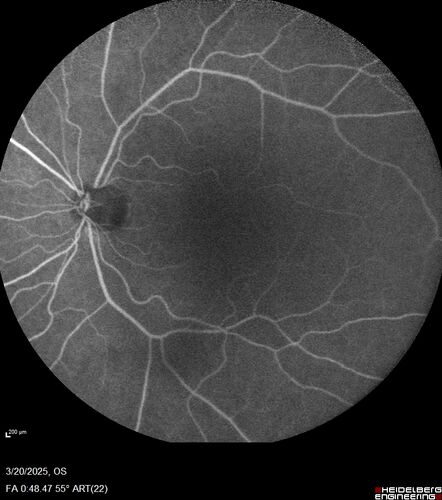

Paclitaxel induced cystoid macular edema - reversed when chemo stopped

74 year old retired physician  About 2-3 weeks ago there was gradual vision loss in the right eye. The patient was seen by an ophthalmologist who saw macular swelling and injected vabysmo. He has been on chemotherapy (Carbiplatin and Carboxytaxol for 2 cancers - advanced prostrate diagnosed 2019 - has had brain surgery AND squamous lung cancers treated with radiation)

Medical Hx: Prostate cancer (Onset: 2018). Pulmonary and bone cancer metastatic. Brain cancer metastasized from prostate cancer.

Surgical Hx: Right frontal & Frontoparietal Craniotomy (Onset: 2024). Appendectomy. Hemorrhoidectomy. Herniorrhaphy. Prostate. Systemic Meds: Chemotherapy. Radiation. Eligard Every 3 Months 22.5 MG per 0.375 ML Prefilled Syringe. MIRALAX prn. Tums Freshers 500 MG Chewable Tablet. Vitamin D. XGEVA.

VA OD: Dcc20/125+1

VA OS: Dcc20/125-2

TP: OD:12 OS:15